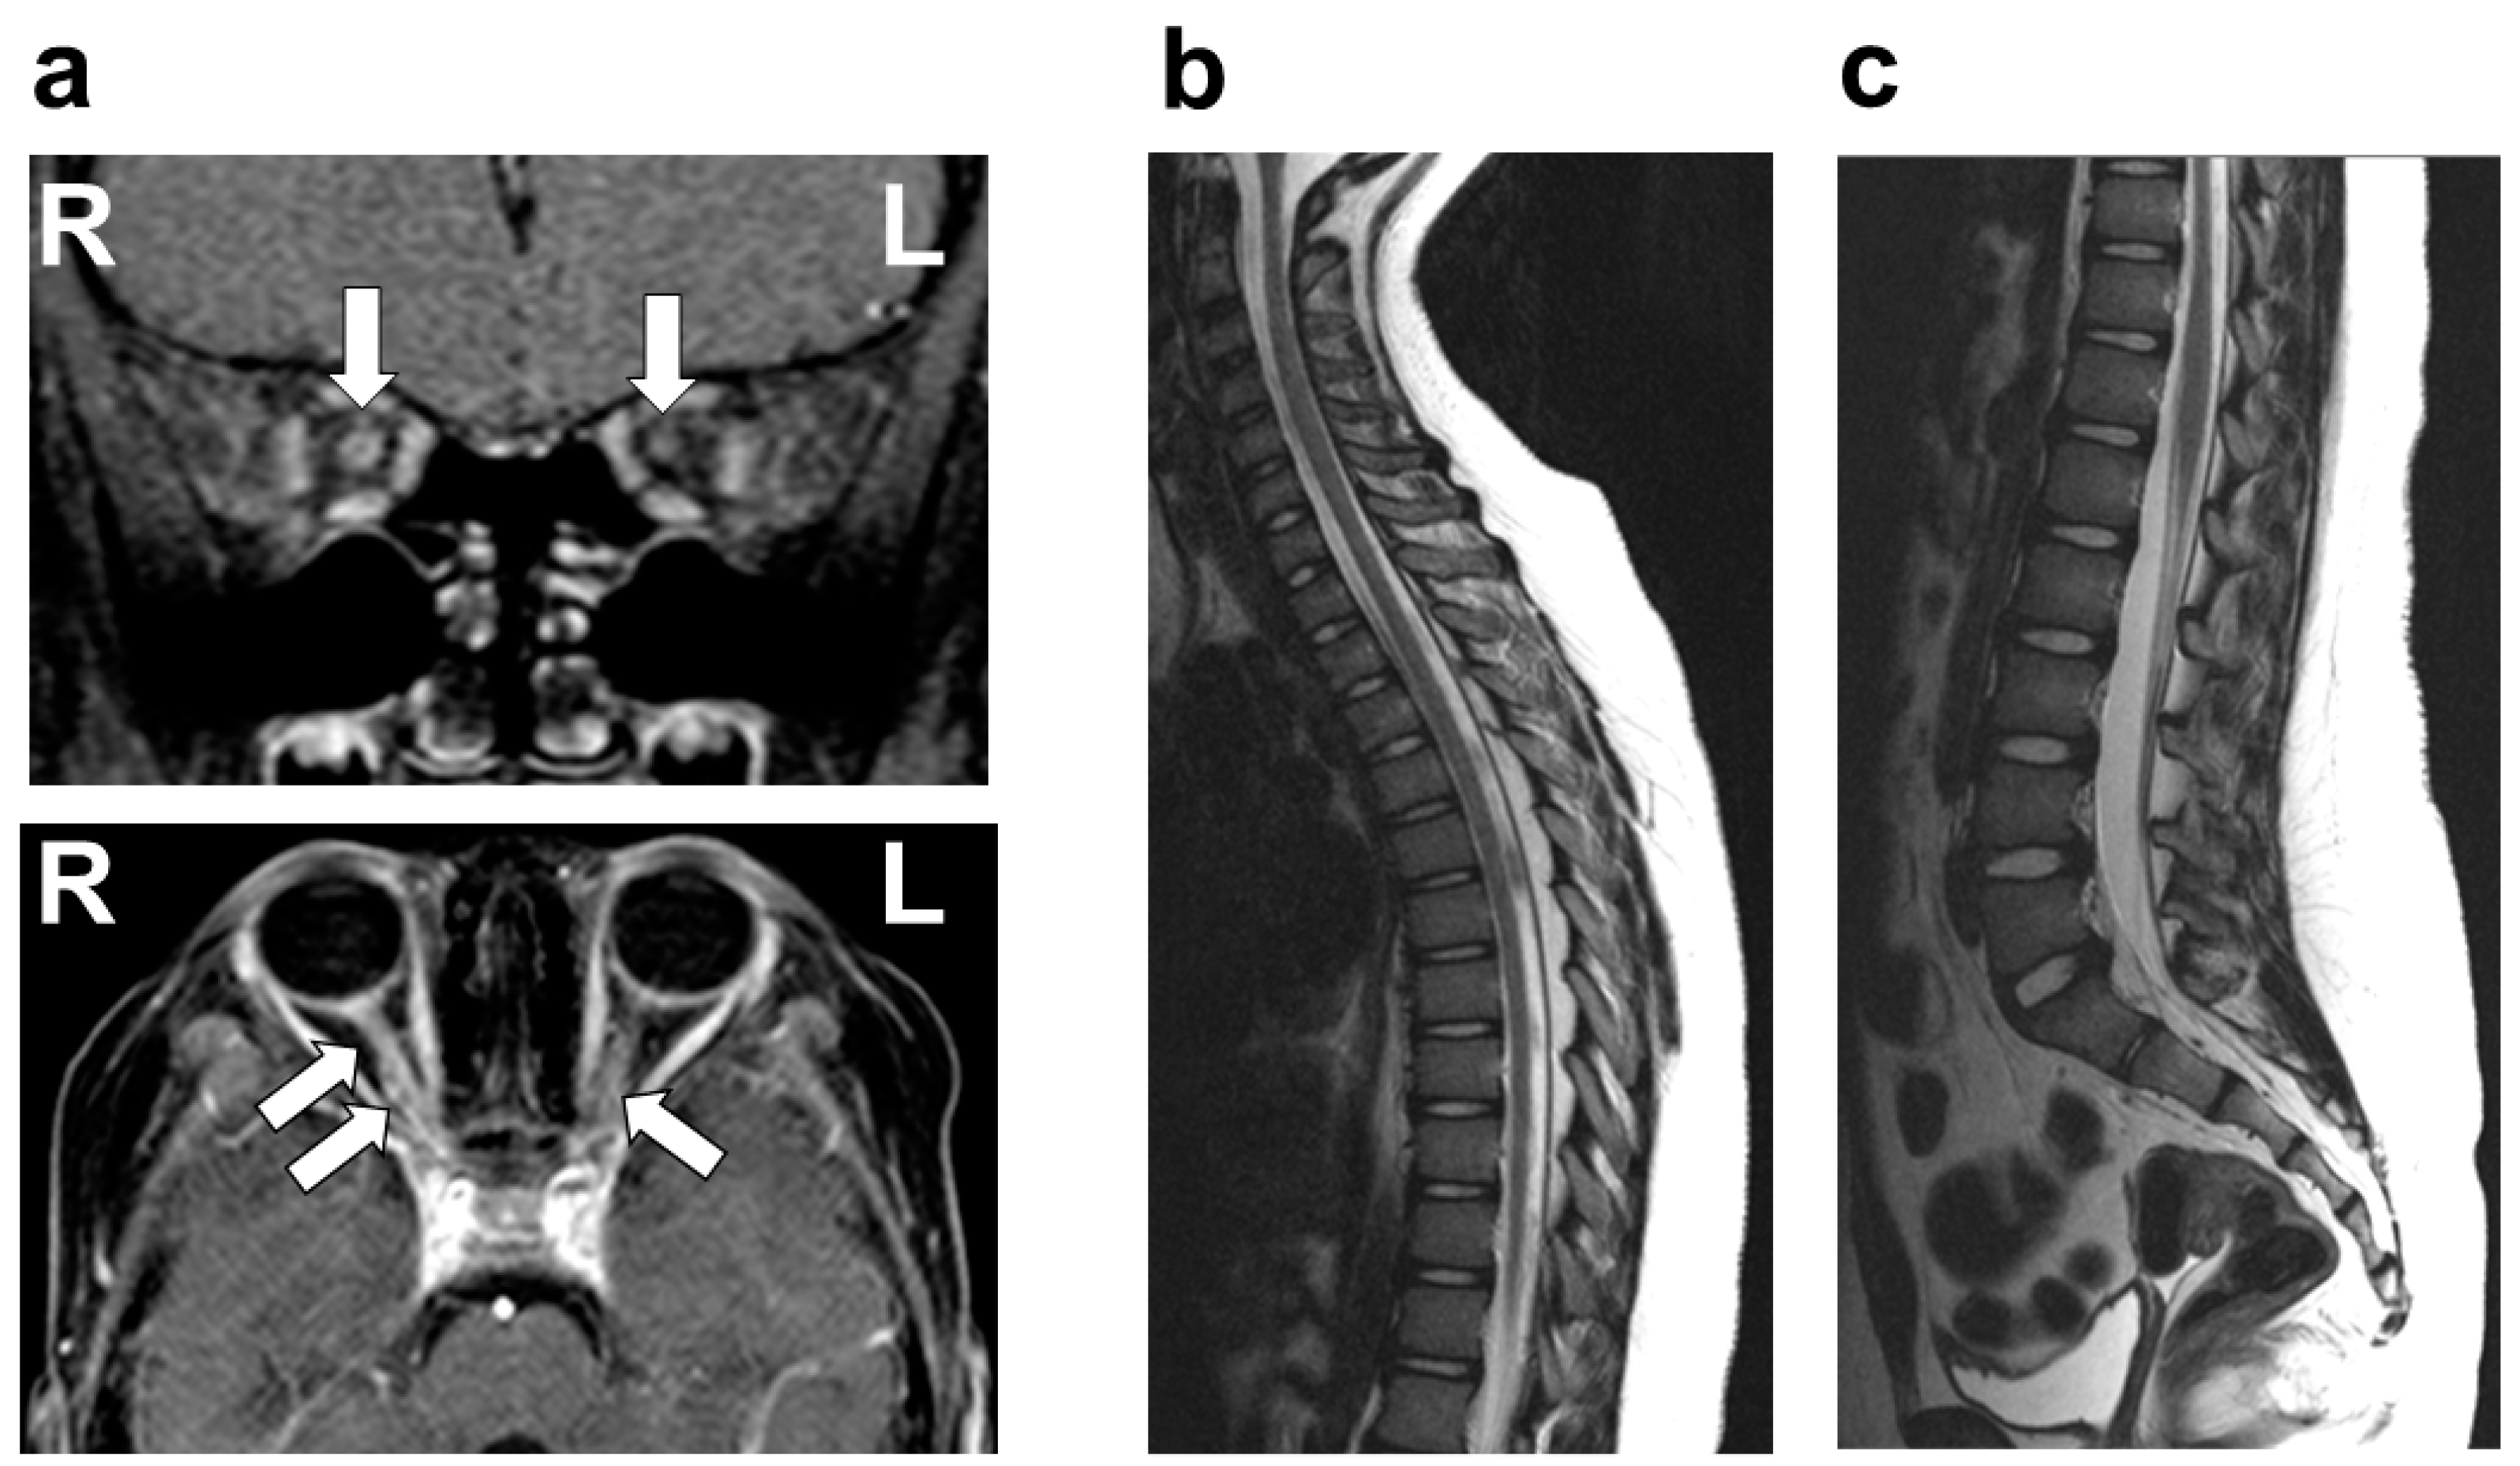

On physical examination, she was afebrile, with no cervical lymphadenopathy. Her pupils measured 6 mm on the right and 4 mm on the left, both showing sluggish light reflexes bilaterally. No other neurological abnormalities were identified, with no evidence of the involvement of cranial nerves other than the optic nerve, including the trigeminal and facial nerves. VA testing revealed no light perception in the right eye, while the left eye demonstrated a VA of 20/30. A fundus examination showed bilateral optic disc redness and inflammatory edema. There was no evidence of involvement beyond the optic nerve, including the uvea, sclera, cornea, conjunctiva, or chorioretina. Optical coherence tomography (OCT) demonstrated pronounced bilateral optic disc swelling, predominantly affecting the right eye. Flash-visual evoked potential (Flash-VEP) revealed prolonged P100 latency bilaterally. A contrast-enhanced MRI of the head revealed significant enhancement of the bilateral optic nerves, predominantly on the left side (Figure 1). No other abnormalities were observed in the brain or spinal cord MRIs (Figure 1). A chest X-ray revealed no pulmonary nodular opacities or hilar lymphadenopathy. The laboratory investigations, including blood counts, biochemical parameters, and coagulation profiles, were unremarkable. Serum tests for antinuclear antibody, dsDNA antibody, anti-SS-A/SS-B antibody, anti-MPO-ANCA antibody, and anti-PR3-ANCA antibody were all negative. The CSF analysis showed normal cell counts, glucose, and protein levels. Further CSF studies revealed that AQP4-Ab (measured via an enzyme-linked immunosorbent assay (ELISA)), MOG-Ab (measured using a live cell-based assay (live CBA)), OCB, and MBP were all negative. Based on these findings, the patient was diagnosed with idiopathic ON.

Figure 1. Brain and spine MRI after the first attack of optic neuritis. (a) Brain gadolinium-enhanced MRI (T1-weighted image) showing significant enhancement of the bilateral optic nerve with right-sided predominance (white arrow). The upper and lower panels represent the coronal and horizontal sections, respectively. (b,c) Thoracic spine MRI (b), and lumbar and sacral spine MRI (c), showing no abnormalities in signal intensity (sagittal T2-weighted image).